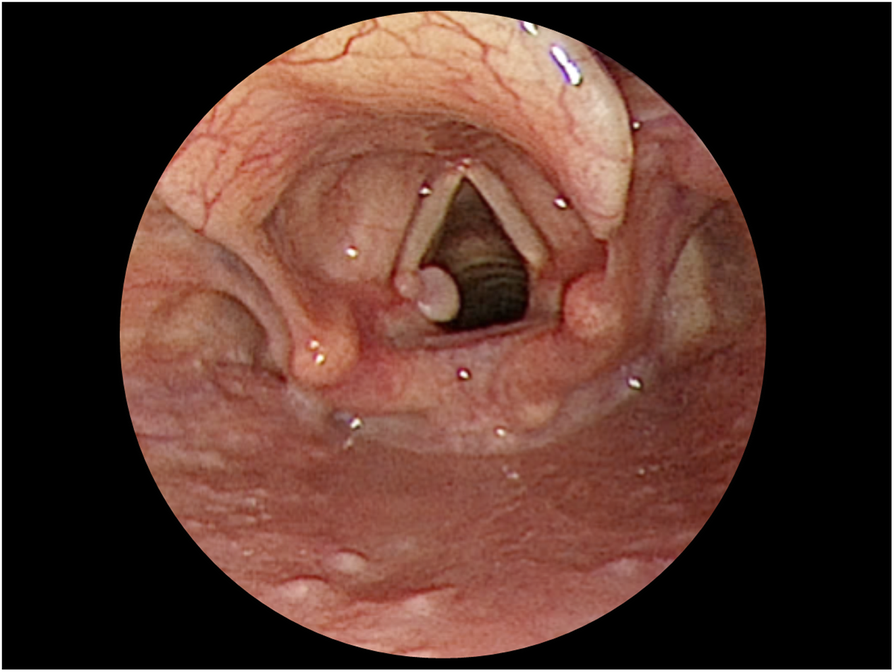

Fig. 3

Vocal cord granuloma in case 2: A granuloma over the posteromedial aspect of the left vocal cord was noted 2 months after transoral right thyroidectomy. The location of the granuloma was similar to that of the granuloma in case 1